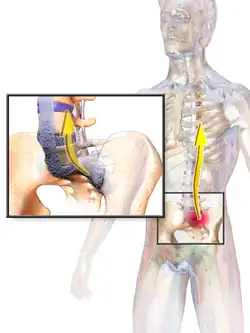

Ankylosing spondylitis (AS) is a type of arthritis from the disease spectrum of axial spondyloarthritis.[5] It is characterized by long-term inflammation of the joints of the spine, typically where the spine joins the pelvis.[2] With AS, eye and bowel problems—as well as back pain—may occur.[2] Joint mobility in the affected areas sometimes worsens over time.[2][6] Ankylosing spondylitis is believed to involve a combination of genetic and environmental factors.[2] More than 90% of people affected in the UK have a specific human leukocyte antigen known as the HLA-B27 antigen.[7] The underlying mechanism is believed to be autoimmune or autoinflammatory.[8] Diagnosis is based on symptoms with support from medical imaging and blood tests.[2] AS is a type of seronegative spondyloarthropathy, meaning that tests show no presence of rheumatoid factor (RF) antibodies.[2]

AS can occur in any part of the spine or the entire spine, often with pain localized to either buttock or the back of the thigh from the sacroiliac joint. Arthritis in the hips and shoulders may also occur. When the condition presents before the age of 18, AS is more likely to cause pain and swelling of large lower limb joints, such as the knees.[13] In prepubescent cases, pain and swelling may also manifest in the ankles and feet where heel pain and enthesopathy commonly develop.[13] Less common occurrences include ectasia of the sacral nerve root sheaths.[14]

Pathophysiology

Ankylosing spondylitis (AS) is a systemic rheumatic disease, meaning it affects the entire body. 1–2% of individuals with the HLA-B27 genotype develop the disease.[11] Tumor necrosis factor-alpha (TNF α) and interleukin 1 (IL-1) are also implicated in ankylosing spondylitis. Autoantibodies specific for AS have not been identified. Anti-neutrophil cytoplasmic antibodies (ANCAs) are associated with AS, but do not correlate with disease severity.[17]

"Bamboo spine" develops when the outer fibers of the fibrous ring (anulus fibrosus disci intervertebralis) of the intervertebral discs ossify, which results in the formation of marginal syndesmophytes between adjoining vertebrae.